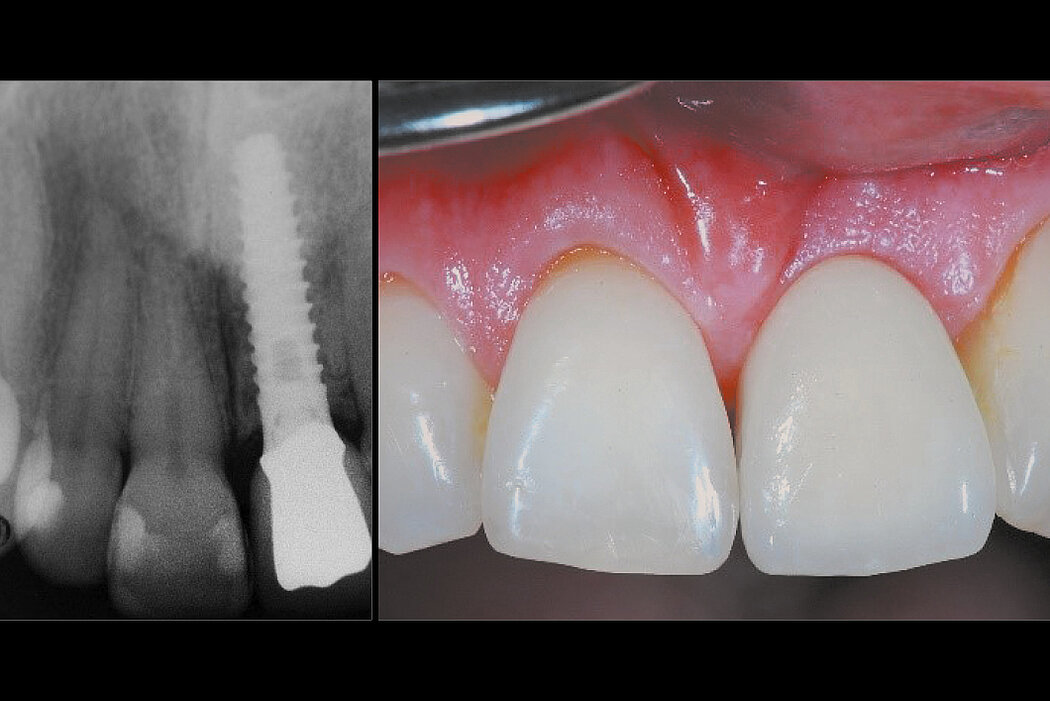

延迟种植的前牙区牙槽嵴保存

病例来自 Prof. Ronald E. Jung

瑞士,苏黎世

目的/方法

前牙区牙齿拔除后的硬组织和软组织保存,以便进行延迟种植。防止在植入种植体时进行广泛的引导骨再生手术。

结论

与自然愈合相比,使用Geistlich Bio-Oss® Collagen 和 Geistlich Mucograft® Seal 可以更好地保存硬组织和软组织。在植入种植体时,行微创GBR,对牙槽嵴进行塑形。

拔牙后即刻与拔牙后10个月的比较